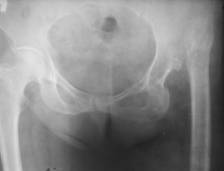

С целью уменьшения мышечной спастики и высоты вывиха бедра в дооперационном периоде накладывается скелетное вытяжение. Оперативное вмешательство производится под комбинированным обезболиванием в положении больной на боку. Разрез для заднебокового доступа к ТБС. Послойно с сопутствующим гемостазом производится доступ и вывих в суставе. Шейка и головка бедренной кости бывают сильно деформированы. Производится остеотомия шейки бедра. Ложе головки бедра заполнено остатками капсулы и фиброзной тканью. После удаления последних обрабатывается вертлужная впадина на положенном месте. При необходимости производится костная пластика или армирование крыши винтами. Установка ацетабулярного компонента производится цементным способом (рис. 1, 2).

Рис. 1

Рис. 2